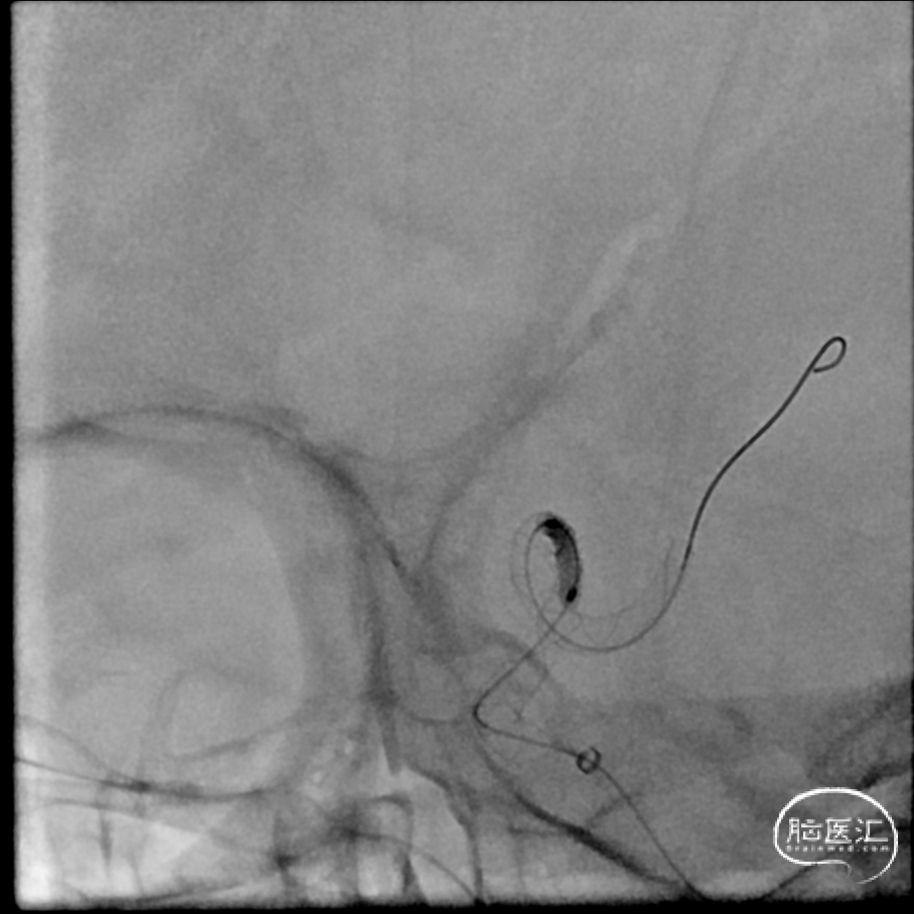

手术过程

6F 90cm长鞘+6F 115cm中间导管

SL-10/synchro .014,5X速度

交换3m Floppy,Gateway 1.5mm/9mm,6atm

Pos-dilatation

Maverick 2mm/15mm,6atm

支架微导管Frepass

nuva 4/40

支架打开不良

支架重新打开良好

回撤微导管造影

再次交换3m Floppy

Maverick 2mm/15mm,6atm